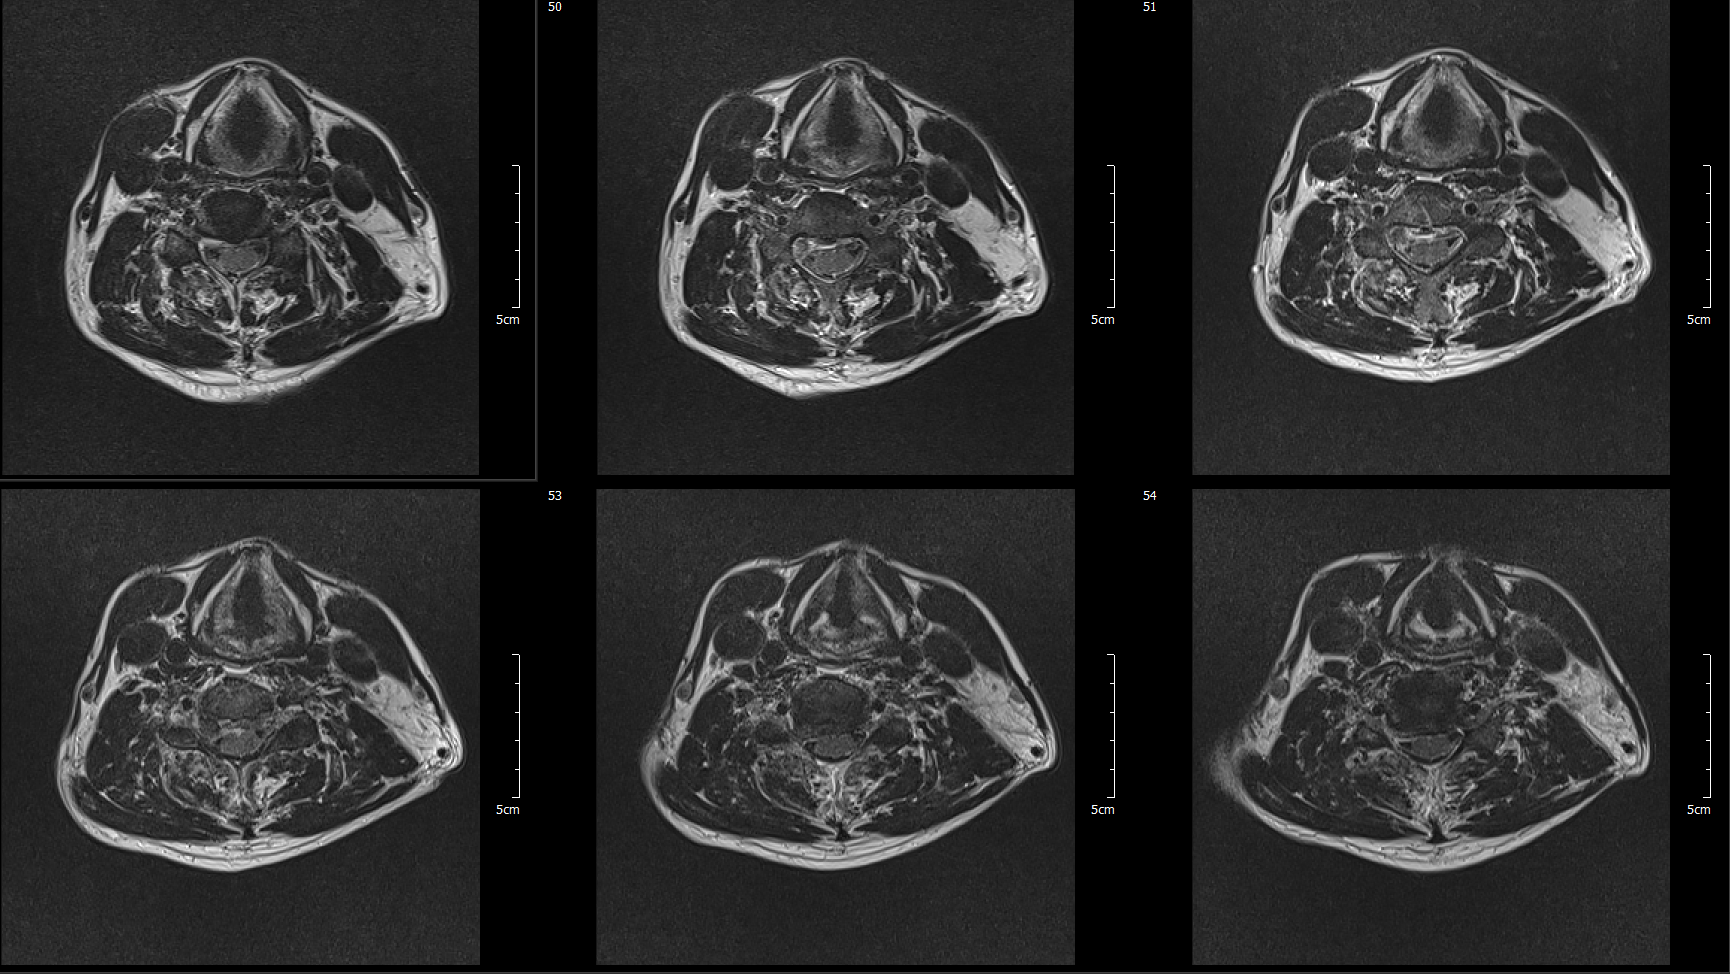

MRI

C5-6 : Ruptured HCD, Rt